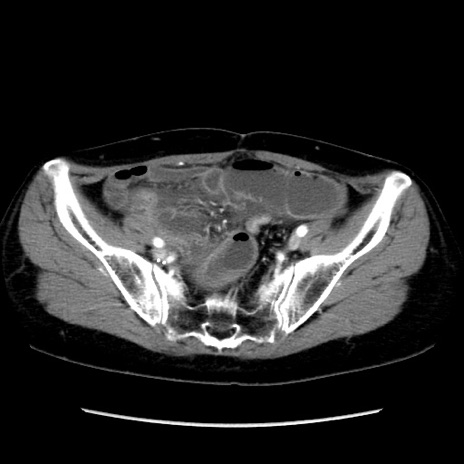

症例32(横断像)

【症例】40歳代 女性

【主訴】上腹部痛、嘔気・嘔吐

【現病歴】約9時間前頃から急に上腹部痛、嘔気、嘔吐が出現。改善しないため救急要請。

【既往歴】子宮頚癌(広汎子宮全摘術、放射線療法)、腸閉塞